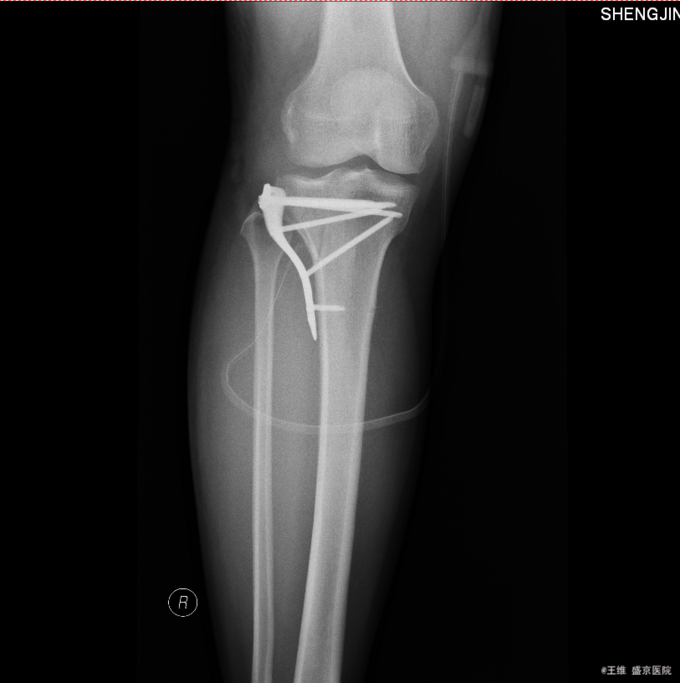

主诉:车祸致右膝部疼痛肿胀活动障碍5小时 现病史:患者及家属代述患者于2015年10月30日下午5点时在走路时被汽车撞伤发生车祸,导致右膝部疼痛肿胀活动障碍,当时无昏迷,送至沈阳中医4院,行DR及影像学检查示:右胫骨平台骨折,右12肋骨骨折。家属为行进一步治疗来我院就诊。经门诊检查后收入我科。患者病来,意识清醒,无头痛头晕,无咳嗽咳痰,无心慌气短,饮食正常,小便正常,大便未排,体重无变化。

专科查体:右小腿近端肿胀明显,无明显开放性创口,痛阳性,叩击痛阳性,可触及骨擦音骨擦感,压痛阳性,,右下肢感觉未见明显异常,右足趾感觉运动未见明显异常,双侧足背动脉搏动良好,末梢血运良好

患者于2015年10月30日因右侧胫骨平台骨折入院,入院后给予消肿止痛对症治疗后,于2015年11月6日在全麻下行右胫骨平台骨折切开复位内固定术,手术顺利,患者安全返回病房。术后常规给予抗炎消肿对症治疗后,待病情稳定后于2015年11月24日遵医嘱出院。